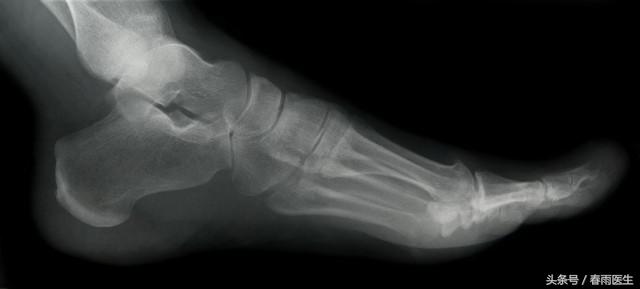

踝关节出现了肿胀、畸形、明显疼痛、并无法再负重行走,甚至在移动后出血,有可能是骨折了。

如果怀疑有骨折的情况,需要及时就医,进行X光检查。再次强调,在医生处理前不要强行移动,或者强行伸展骨折部位,这样可能会让骨折加重。如果骨折部分变形,且身体其他部位的皮肤变凉,苍白无血色,甚至范蓝,可以轻轻地将肢体纵向拉伸。骨折也分不同的情况:

-

没有移位的踝关节骨折可通过石膏固定来治疗;

不能仅用手法复位或复位后石膏固定不能维持原位的踝关节移位骨折,常需手术治疗。